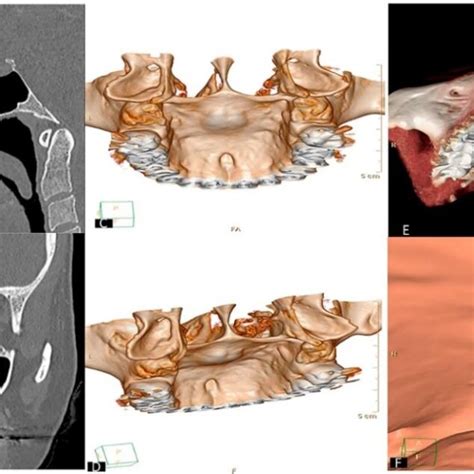

Cuando acudas al odontólogo por un bulto en el paladar, este realizará una exploración clínica detallada. Examinar la apariencia y palpación: Observo el tamaño, color, forma y localización del bulto. Historia clínica: Te preguntaré desde cuándo notaste el bulto, si ha crecido, si hubo algún desencadenante (una quemadura, un golpe, un diente con dolor), hábitos como fumar o beber, etc. Pruebas complementarias: Dependiendo de lo que sospeche, puedo solicitar una radiografía (por ejemplo, una radiografía periapical o panorámica si sospecho de un origen dental o un diente extra), o incluso una biopsia.

- Ortopantomografía: para contar con una visión panorámica de toda la situación.